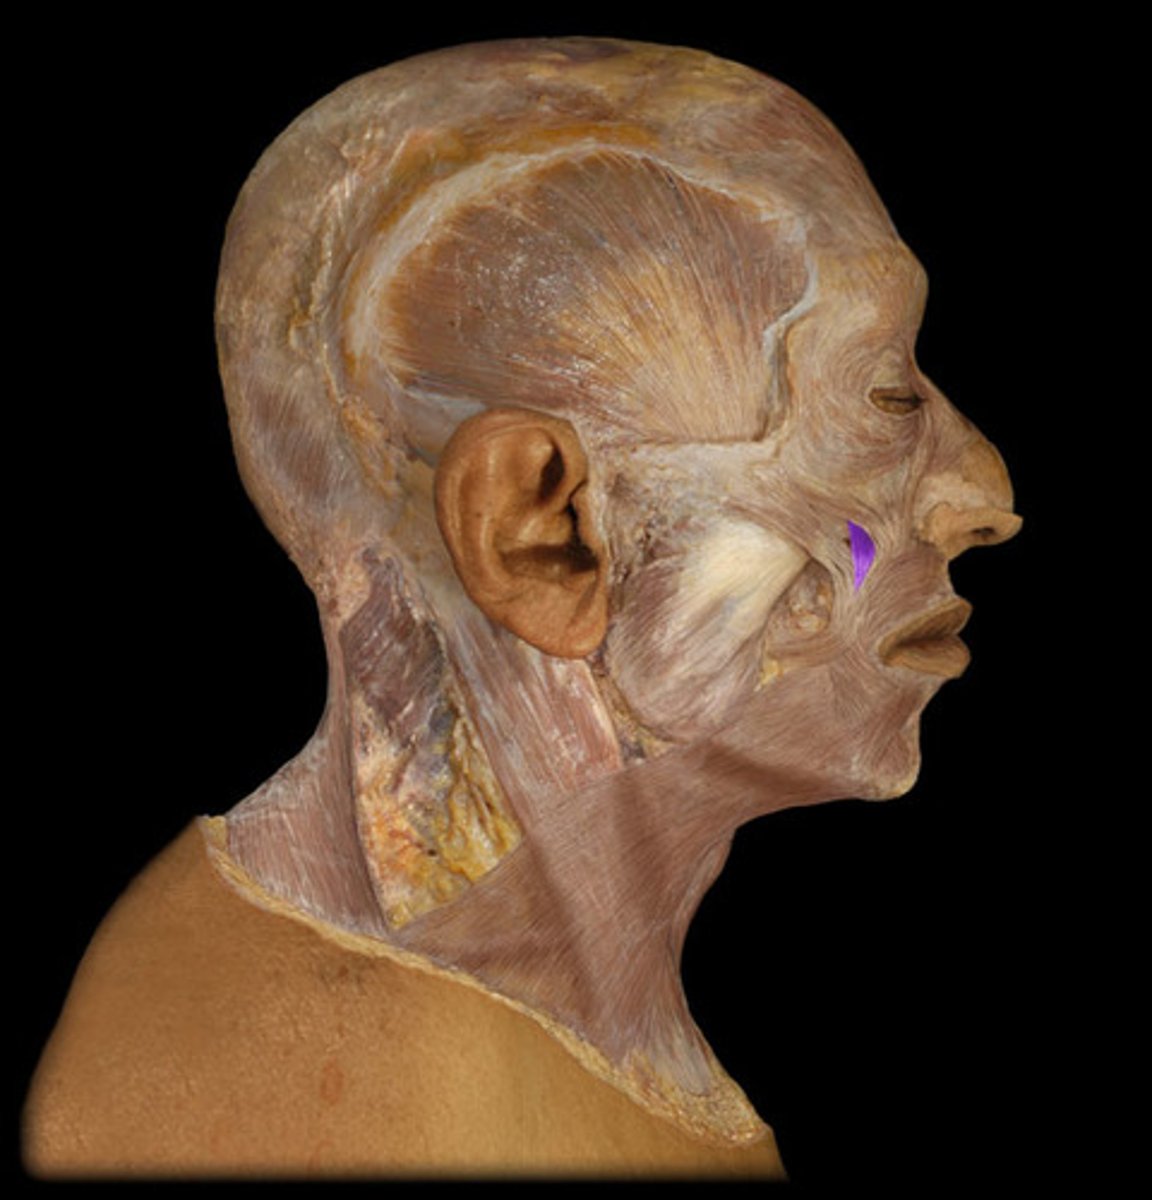

Lateral pterygoid